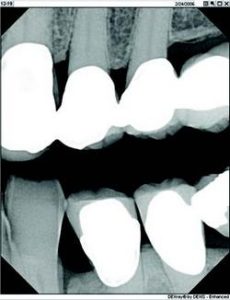

I am often looking for subtle changes in tooth structure that can be difficult, if not impossible, to distinguish. My digital system provides me with a variety of enhancement tools. I am able to click-and-drag on each image to change its contrast. You can’t do that with film.

One feature that I particularly like with my system is the ability to take vertical bitewing images. So many of our patients have a long crown-to-root ratio, and I see it as a distinct advantage to have the option of vertical, not just horizontal, bitewings (Fig. 1).”